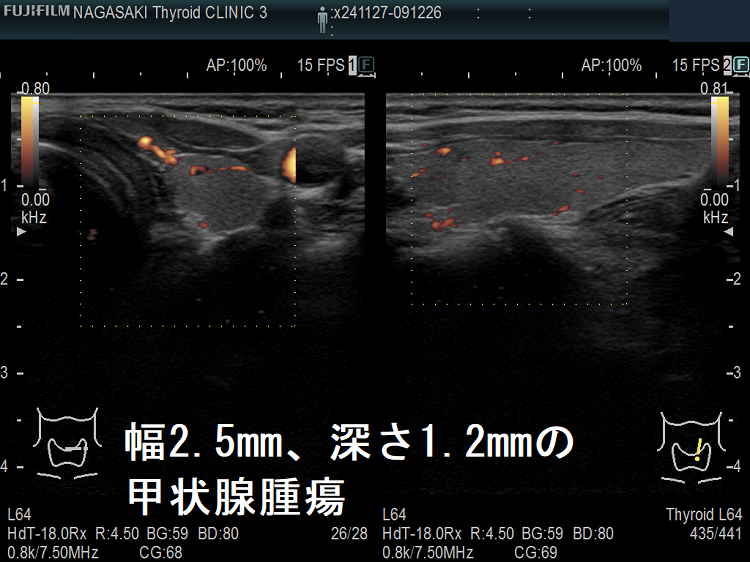

超高解像度:なんと2mm未満の甲状腺腫瘍もみつかる!?

Unbelievable! 超高解像度のため、2mm未満の甲状腺腫瘍、3mm未満の甲状腺微小乳頭癌もみつかります。小さすぎて、穿刺細胞診も不可能、エラストグラフィ-も無効です。

ケース③ 幅2.5mm、深さ1.2mmの甲状腺腫瘍

幅2.5mm、深さ1.2mmの甲状腺腫瘍 超音波(エコー)画像

幅2.5mm、深さ1.2mm、高さ1.6mm の甲状腺腫瘍 超音波(エコー)画像;B-モードでは甲状腺のう胞(甲状腺嚢胞)甲状腺腫瘍か判別できません。

幅2.5mm、深さ1.2mmの甲状腺腫瘍 超音波(エコー)画像 パワードプラー

幅2.5mm、深さ1.2mm、高さ1.6mm の甲状腺腫瘍 超音波(エコー)画像 パワードプラーモード; 内部微細血流を確認できるため、甲状腺腫瘍であるのが判ります。

[eFlow(イー フロー)]で内部微細血流を確認できるため、甲状腺腫瘍なのが判ります。

幅2.5mm、深さ1.2mmの甲状腺腫瘍 超音波(エコー)画像(拡大)

幅2.5mm、深さ1.2mm、高さ1.6mm の甲状腺腫瘍 超音波(エコー)画像 パワードプラーモード(拡大)

幅2.5mm、深さ1.2mmの甲状腺腫瘍 超音波(エコー)画像eFlow(拡大)

幅2.5mm、深さ1.2mm、高さ1.6mm の甲状腺腫瘍 超音波(エコー)画像 eFlow(イー フロー)モード(拡大)